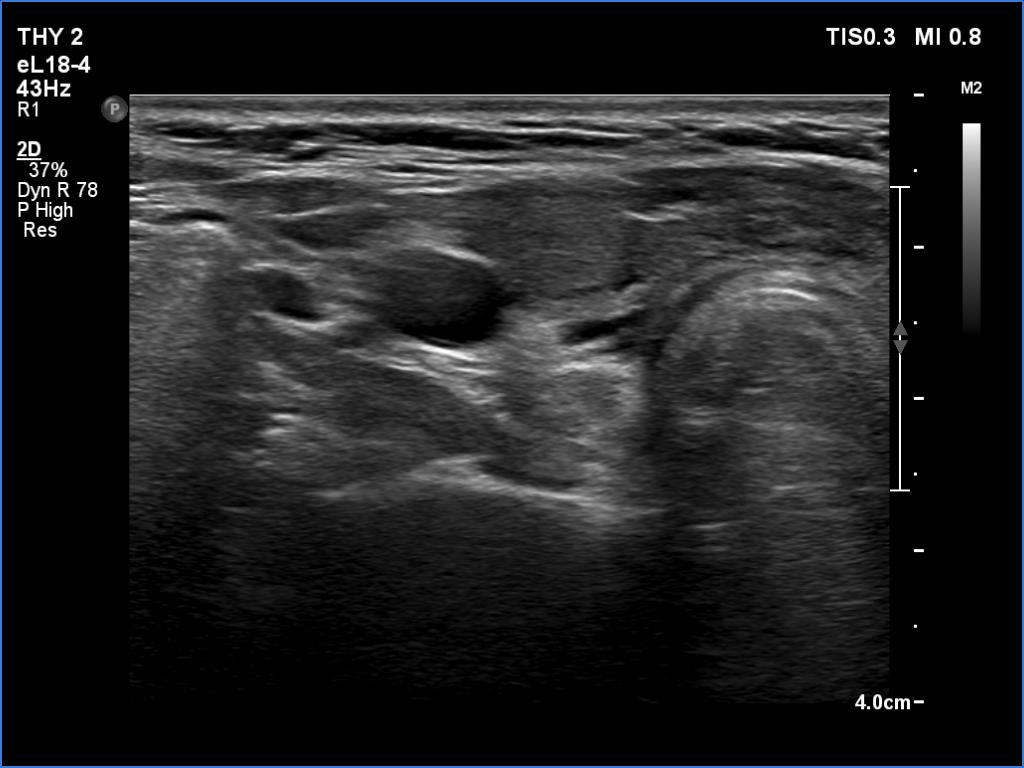

Second examination 3 months later (ultrasonographic picture 2)

Right lobe, another transverse scan. There is an echonormal or less hypoechoic lesion in the ventral part of the lobe.